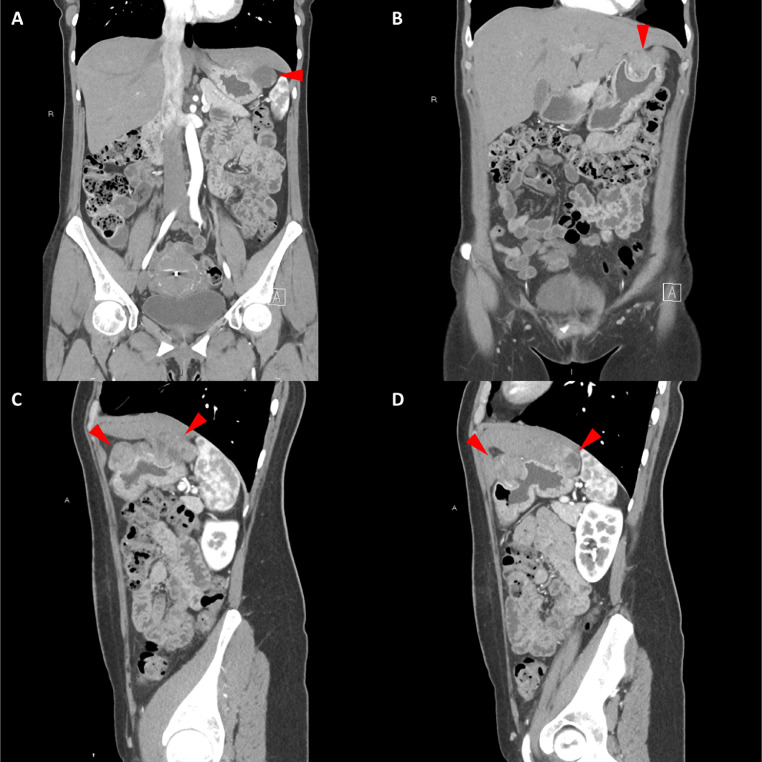

胸部、腹部和骨盆的對(duì)比增強(qiáng)動(dòng)脈和靜脈期 CT 顯示多個(gè)圓形、主要是血管豐富的異質(zhì)腫塊,具有囊性和實(shí)性成分,起源于胃底和胃體(圖 2-4)。 病變部分呈外生結(jié)構(gòu),被認(rèn)為位于粘膜下層。 在頸部多發(fā)同步性副神經(jīng)節(jié)瘤的情況下,賊初的鑒別診斷包括多發(fā)性副神經(jīng)節(jié)瘤、多發(fā)性 GIST 以及轉(zhuǎn)移性疾病。

Fig. 3

圖 3:多個(gè)胃腸道間質(zhì)瘤的冠狀和矢狀圖像。 (A 和 B)冠狀動(dòng)脈相對(duì)比增強(qiáng) CT 圖像顯示胃賁門產(chǎn)生的外生性腫塊。 (C 和 D)矢狀動(dòng)脈相位對(duì)比增強(qiáng)圖像顯示腫塊的異質(zhì)性和外生結(jié)構(gòu)。